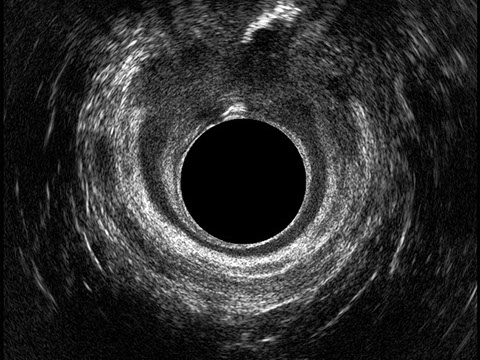

L’ecografia transanale è un esame diagnostico per immagini che consiste nell’introduzione di un trasduttore ad ultrasuoni. Le immagini qualitativamente migliori del canale anale sono ottenute usando un trasduttore rotante, montato in un manipolo rigido, che fornisce un’immagine a 360°. Con le apparecchiature più moderne è anche possibile ottenere immagini tridimensionali.

L’ecografia transanale permette di distinguere la sottomucosa che riveste il canale anale, lo sfintere anale interno, e lo sfintere anale esterno.

Le principali indicazioni all’esecuzione di tale esame sono lo studio dell’integrità delle strutture muscolari nei casi di incontinenza fecale, lo studio topografico dei processi settici perianali (ascessi e fistole) e lo studio dei processi proliferativi epiteliali (carcinoma anale).